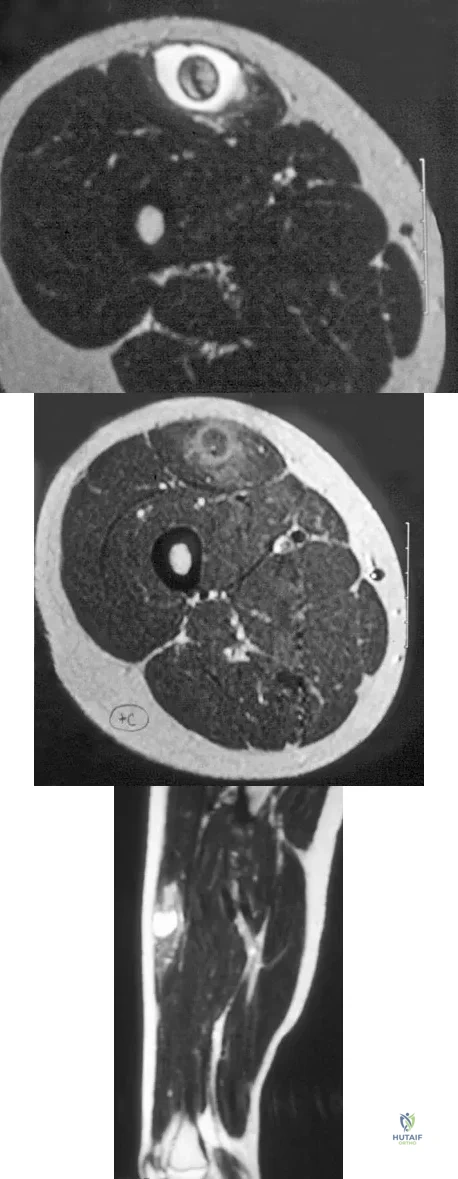

Figures 48a through 48c show the lateral radiograph and MRI scans of a 60-year-old man who has had pain in his thigh for 1 month. The next most appropriate step in management should consist of

Explanation